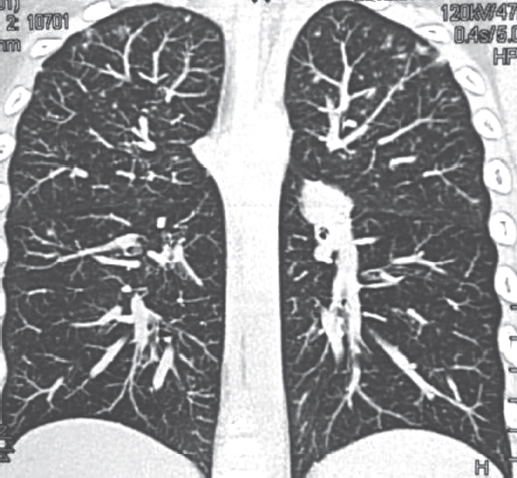

МСКТ грудной полости 04.06.2012 (рис. 2, а, b): «КТ-картина множественных двусторонних субплевральных инфильтратов легочной ткани, двусторонний гидроторакс. Выраженная гепатоспленомегалия. Лимфоузлы средостения и корней легких стабильны, по сравнению с МСКТ от 20.02.2012 с признаками кальцинации в прежнем объеме». Исследования на МБТ мокроты, промывных вод бронхов (микроскопия, полимеразная цепная реакция, посев) отрицательны».

Рис. 2. Пациент, 6 лет. Компьютерная томография грудной клетки от 04.06.2012: множественные двусторонние субплевральные инфильтраты в легких, двусторонний гидроторакс (а — аксиальная проекция, b — фронтальная проекция)

Fig. 2. Patient, 6 years old. Computed tomography of the chest, 04.06.2012: multiple bilateral subpleural infiltrates in the lungs, bilateral hydrothorax (а – axial projection, b – frontal projection)

После консультации фтизиатра специфический характер диссеминации в легких отвергнут. В связи с возможностью прогрессирования туберкулеза 07.06.2012 возобновлена противотуберкулезная терапия тремя противотуберкулезными препаратами — изониазидом, пиразинамидом, этамбутолом.